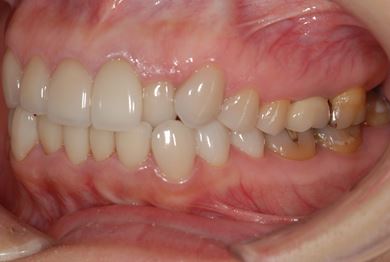

セラミックの症例写真 SHINBI

セラミック治療+ラミネートベニア治療

| 治療内容 | ジルコニアオールセラミッククラウン1本(オールセラミック用土台1本)、オールセラミッククラウン9本(オールセラミック用土台1本)、オールセラミックラミネートベニア11本 | ||||||||||||||||||||||||||||||||